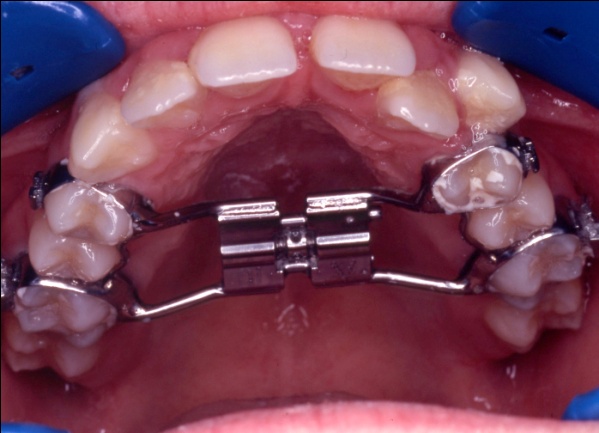

2 - Appareillage utilisé : expansion palatine et multiattaches

Cette étape montre l’utilisation d’un disjoncteur palatin pour élargir le maxillaire. Contrairement à la mandibule, le palais présente une suture médiane, véritable joint de croissance, que l’on peut activer chez l’enfant ou l’adolescent. En écartant progressivement les deux moitiés du maxillaire, on crée un gain d’espace réel, non dentaire. Cela permet de rétablir une largeur d’arcade suffisante, sans extraction, en amont de l’alignement multiattaches.